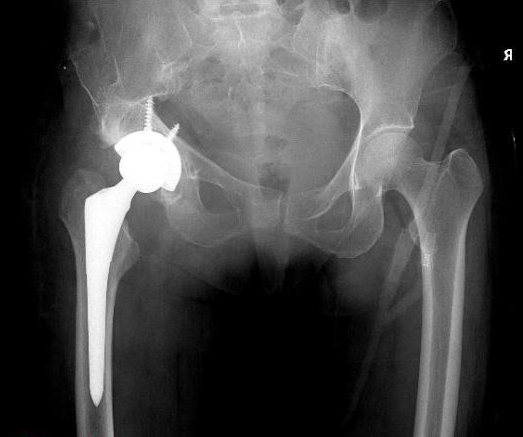

2020年,南方医科大学附属中西医结合医院进行了人工关节置换手术,减轻了患者20多年的痛苦。使用3D打印计算机辅助手术的“个性化”治疗计划是使用CT图像,计算机三维重建,等设计模拟技术,这些技术可以在手术前从多个角度进行观察最大限度地处理困难和复杂的操作。降低患者手术风险的能力。